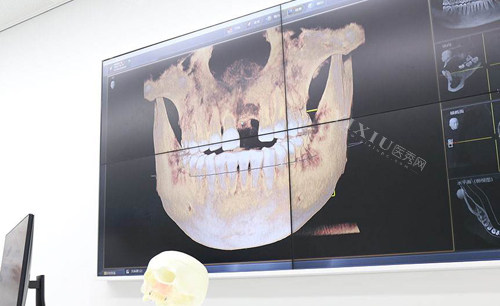

神经损伤也是种植牙可能出现的后遗症,如果在植入种植体的时候没有避开神经,就可能会导致神经损伤,因此在选择种植牙医生方面一定要注意,技术过硬的口腔医生在手术过程中一般都会避免这个问题。

从上述副作用不难看出,种植牙手术的后遗症多和医生技术以及医疗条件有关,比如说手术环境,有实力的口腔医院会有专门的手术室,来降低感染风险,而有些牙科诊所条件比较简陋,没有手术室,那么做种植牙手术感染的几率就比较高。